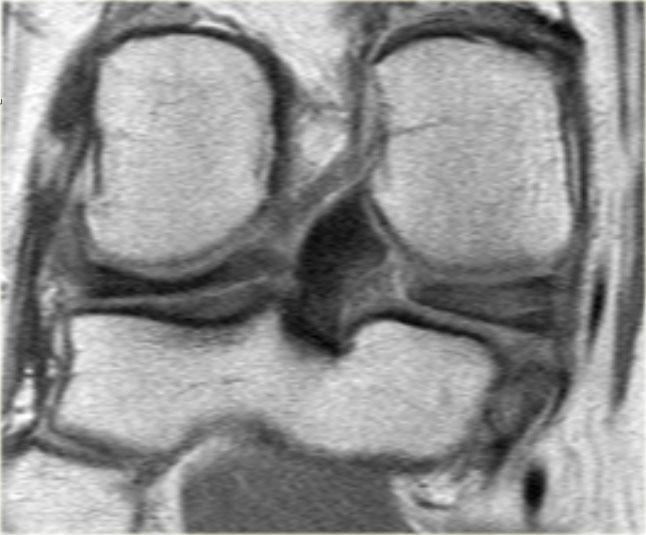

Bên trái là một trường hợp khác của sụn chêm ngoài bị lật.

- Lưu ý sừng trước rất lớn.

Phần trong là sừng sau đã bị di lệch. - Phần trong chạy vào hố gian lồi cầu.

- Phần bị di lệch được nhìn thấy rõ ràng như là ‘cấu trúc thứ ba’

trong hố gian lồi cầu. - Điểm nối với phần còn lại của sừng sau.

- Điểm nối với phần còn lại của sừng sau.

- Phần còn lại rất nhỏ của sừng sau.